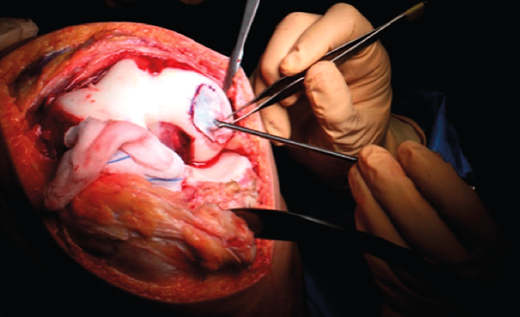

1. A paramedial joint incision is made, with luxation of the knee and access to the lesion (Figure 6).

2. The damaged cartilage is cleaned using curettes, with debridement of the defect, and the lesion is left with healthy and exposed subchondral bone (Figure 7).

3. A surgical marker is used to mark the margins of the lesion, and a mould of the lesion is obtained with a piece of glove (Figure 8).